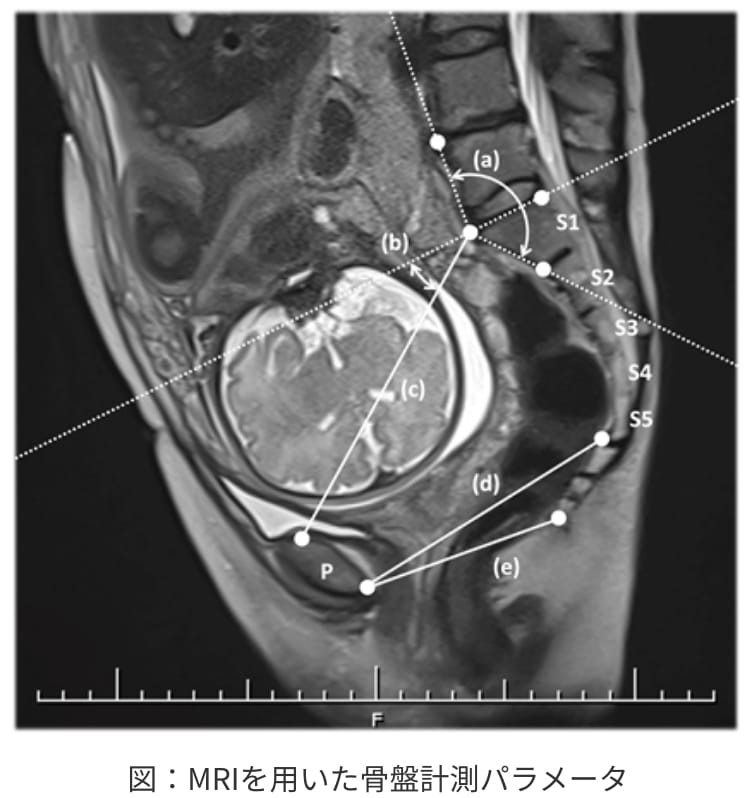

MRIを用いた骨盤計測

児頭骨盤不均衡は、赤ちゃんの頭の大きさと母体の骨盤の大きさに不一致があり、分娩の生理的な進行が妨げられることです。分娩停止による器械分娩や緊急帝王切開の原因になり、赤ちゃんにとっても母体にとっても悪影響を及ぼす可能性があります。

予測には、従来よりX線を用いた骨盤の計測と超音波検査が用いられてきました。しかしこれらは、赤ちゃんが放射線に曝露されることや、正確性が低いため有用性には制限があります。

近年、MRIを用いた骨盤計測法が発達しており、放射線への曝露がないことや、正確性が高いこと、また従来の検査法では評価できない部分を描出することができる利点が注目されています。特に骨盤の出口に近い部分の骨盤計測が可能になったことで、これまでは陣痛開始後に分娩停止で緊急帝王切開を必要する症例を抽出し、母体や赤ちゃんへのリスクを回避できる可能性があります。

当院では、この技術を用いて分娩前の骨盤計測から、児頭骨盤不均衡を早期に認識することや、臨床応用によって母体や赤ちゃんのリスクを回避する方法に関して研究しています。

今回、我々の研究成果が英語論文となり公開されました。

Ryuichi Shimaoka, Yuichiro Takahashi, Hitomi Ono, Masako Matsui, Kazuhiko Asai, Shigenori Iwagaki. Magnetic resonance imaging pelvimetric measurements as predictors for emergent cesarean delivery in obstructed labor. European Journal of Obstetrics & Gynecology and Reproductive Biology: X 19 (2023)100216